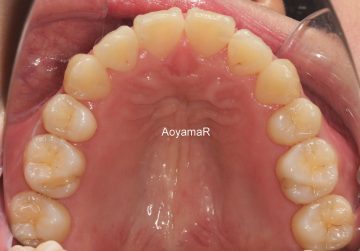

そう生(歯並びのガタガタ、乱杭歯、八重歯)の矯正症例

CASE 42

(28歳 男性 )

上下小臼歯4本抜歯による治療

治療前

治療後